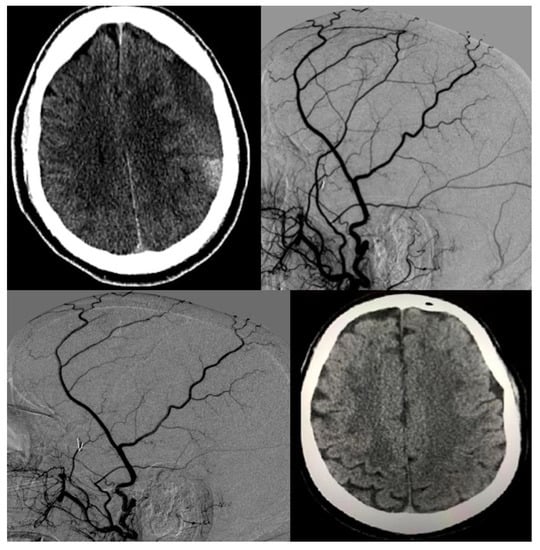

Figure 2.

A 68-year-old man with medical history of hypertension and chronic non-valvular atrial fibrillation on coumadin had a minor motor vehicle accident with whiplash injury but no loss of consciousness. Post-trauma emergent non-contrast CT (NCCT) of the head revealed no evidence of subdural hemorrhage. Patient was asked to resume his normal activities as well as continue with anticoagulation regimen. Three weeks later while vacationing in another state, the patient developed subtle speech difficulties, gait disturbance as well as occasional memory lapses. Emergent NCCT was done which revealed bifrontal subdural hematoma (left worse than right) with acute on chronic component and midline shift. He underwent bifrontal burr hole surgeries but had a fresh re-hemorrhage a week later. The patient flew back to home state where another NCCT was prompted by clinical worsening, including coordination difficulties and word-finding difficulties. This revealed significant worsening from acute on chronic SDH as well as midline shift (top left). Patient was taken for emergent MMA embolization, and the images shows pre-embolization (top right) and post-embolization (bottom left) angiograms. Patient then had monthly clinical and radiological (NCCT) follow-ups. Anticoagulation was stopped throughout this period. Four months later, the patient had near resolution of his SDH after which antiplatelets were started. After another month, anticoagulation was started. The last control NCCT was done 3 months after resumption of anticoagulation and is shown in the image on the bottom right.